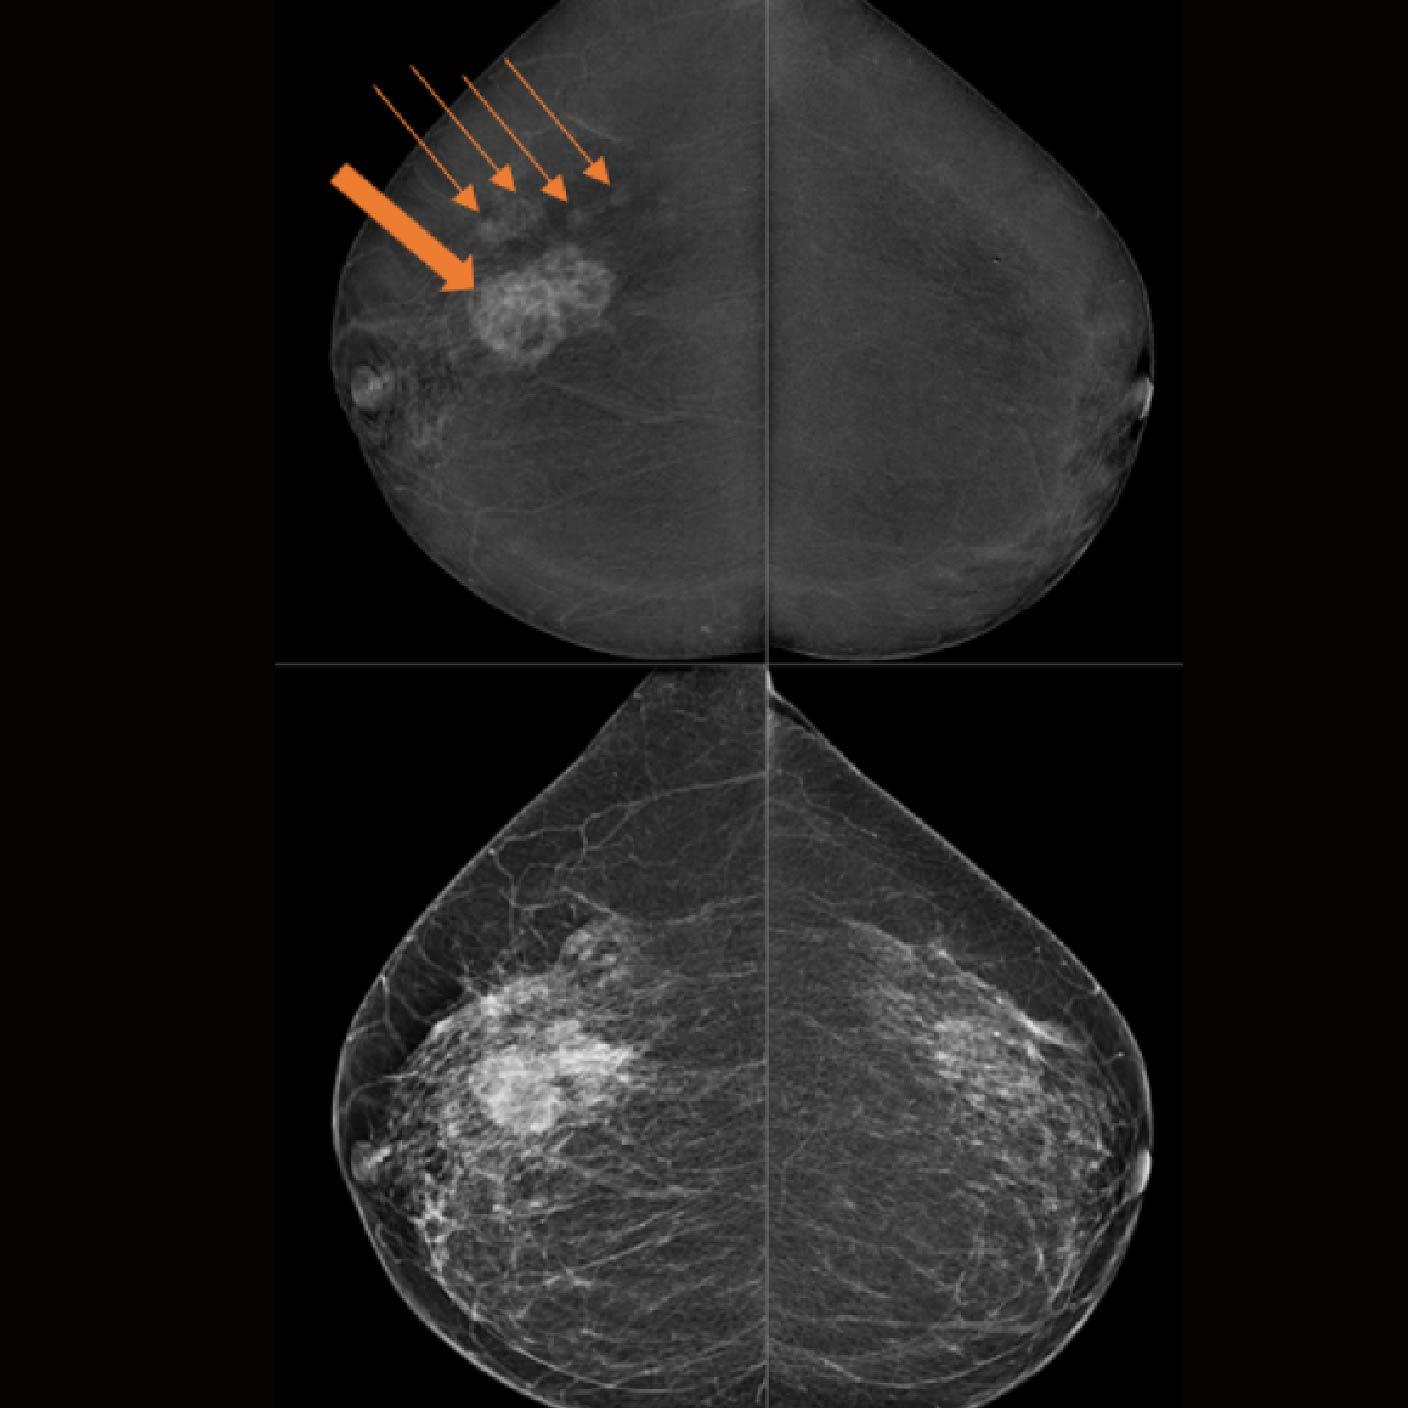

Valoración con TiCEM

- Confirmación de una masa asimétrica en el cuadrante externo de la mama derecha.

- Detección de otros 4 focos (flechas) que muestran realces variables en un diámetro total de aprox. 70 mm

- Se asigna un Bi-RADS 5 en la mama derecha y un Bi-RADS 1 en

la mama izquierda

La patología reportada fue un carcinoma ductal in situ grado 2 (9 horas) y un carcinoma ductal in situ grado 3 (10 Horas) en la mama derecha.